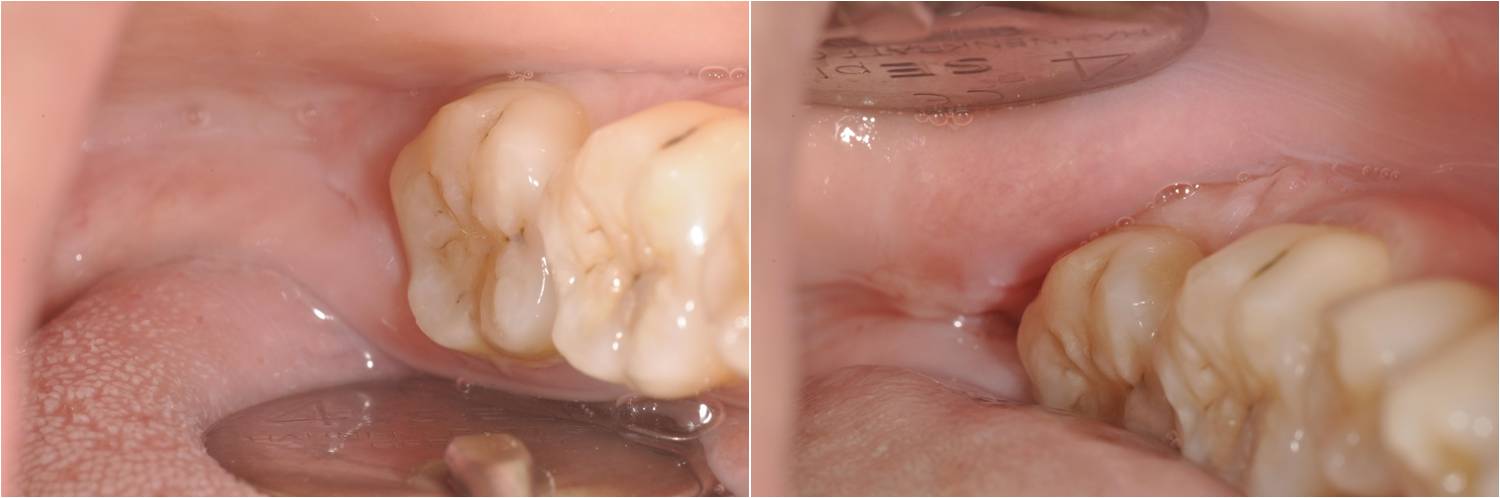

左下阻生齒術前口內狀況

術前、術後比較